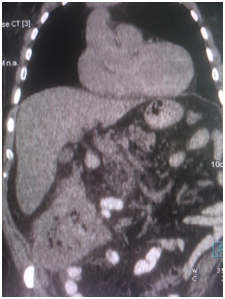

КТ брюшной полости от 21.03.16 – в слепой кишке объемное образование размерами до 98×118×108 мм, параколитическая клетчатка инфильтрирована, в окружающей клетчатке множественные лимфоузлы;

Выполнено ПЭТ/КТ исследование с 18F-ФДГ.

Выявлен гиперметаболический опухолевый процесс в области слепой и восходящей ободочной кишки (SUVmax 21,9), окружающая параколитическая клетчатка неравномерно инфильтрирована, с небольшим количеством жидкостного содержимого. Просвет кишки неравномерно сужен. В окружающей параколитической клетчатке, брыжейке тонкой кишки, отмечаются лимфоузлы,  размерами до 6-8 мм по КО, с умеренным накоплением РФП, SUVmax 4,3.

IMG_4389-27-09-18-09-40.JPG IMG_4389-27-09-18-09-40.JPG IMG_4389-27-09-18-09-40.JPG IMG_4389-27-09-18-09-40.JPG